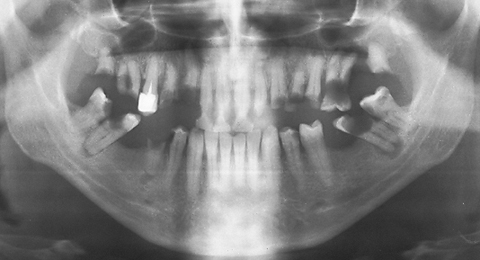

RO graph - ZX-27 sample 3 after-treatment

Patient: L.D., man 48 years old

Diagnosis: D. Adentio partialis superior et inferior

The dental formula after treatment for this case is:

The treatment of this case uses dentures for the upper and lower jaw with arch stabilization and two glass bearings in the fields of  16  and  36 . This patient had intended to place implants in order to not have removable dentures. He is very happy now with the glass pillars ZX-27 treatment.

Treatment was finished on July 2, 2010, and the X-ray inspection is from same day. The patient has very good spirits, he eats and chews normally.